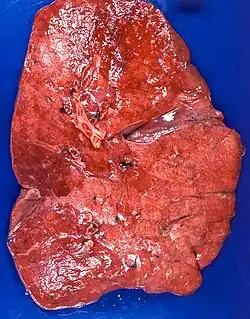

The gross appearance of a lipoid pneumonia changes during different stages of the disease. The lung can appear gray, yellow, or gray-white and may exude oil or form nodules or cavities.[3]